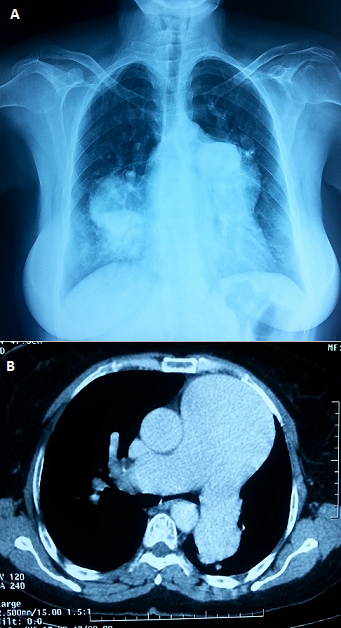

A 34-year-old woman with history of post rheumatic mitral stenosis since the age of 12 years at the stage of surgery (the patient refused it). She was admitted for cough and dyspnea of acute onset without fever or chest pain. The patient was in respiratory distress, afebrile and hemodynamically stable. Arterial blood gas analysis showed PaO2 = 48mmHg, PaCO2 = 56mmHg and pH = 7.26. Clinical examination found signs related to mitral stenosis and congestive heart failure. The electrocardiogram showed atrial fibrillation. Chest radiography showed no signs of pneumonia but highlighted cardiomegaly with a prominent left median arc and ectasia of the lower right arc (A). Doppler echocardiography showed a tight mitral stenosis with mitral area of 0.6 cm2 and a dilated left atrium and right cardiac cavities. It also revealed a significant tricuspid regurgitation and a major pulmonary hypertension with a systolic pulmonary artery pressure at 97 mmHg. The chest CT objectified aneurysmal dilatation of the pulmonary artery (8.2 cm) and its branches without signs of pulmonary embolism (B). The patient improved after non-invasive ventilation and diuretic treatment. Proximal pulmonary artery aneurysms, defined by a ratio of pulmonary artery to aortic diameter greater than two, are rare and bilateral aneurysms were exceptionally described. The causes are dominated by infectious diseases, inflammatory arteritis, and congenital heart disease and acquired valvular heart disease. Pulmonary arterial hypertension can cause chronic aneurysm of the pulmonary artery by direct infringement of the wall with atherosclerosis, medianecrosis and aneurysmal distension.